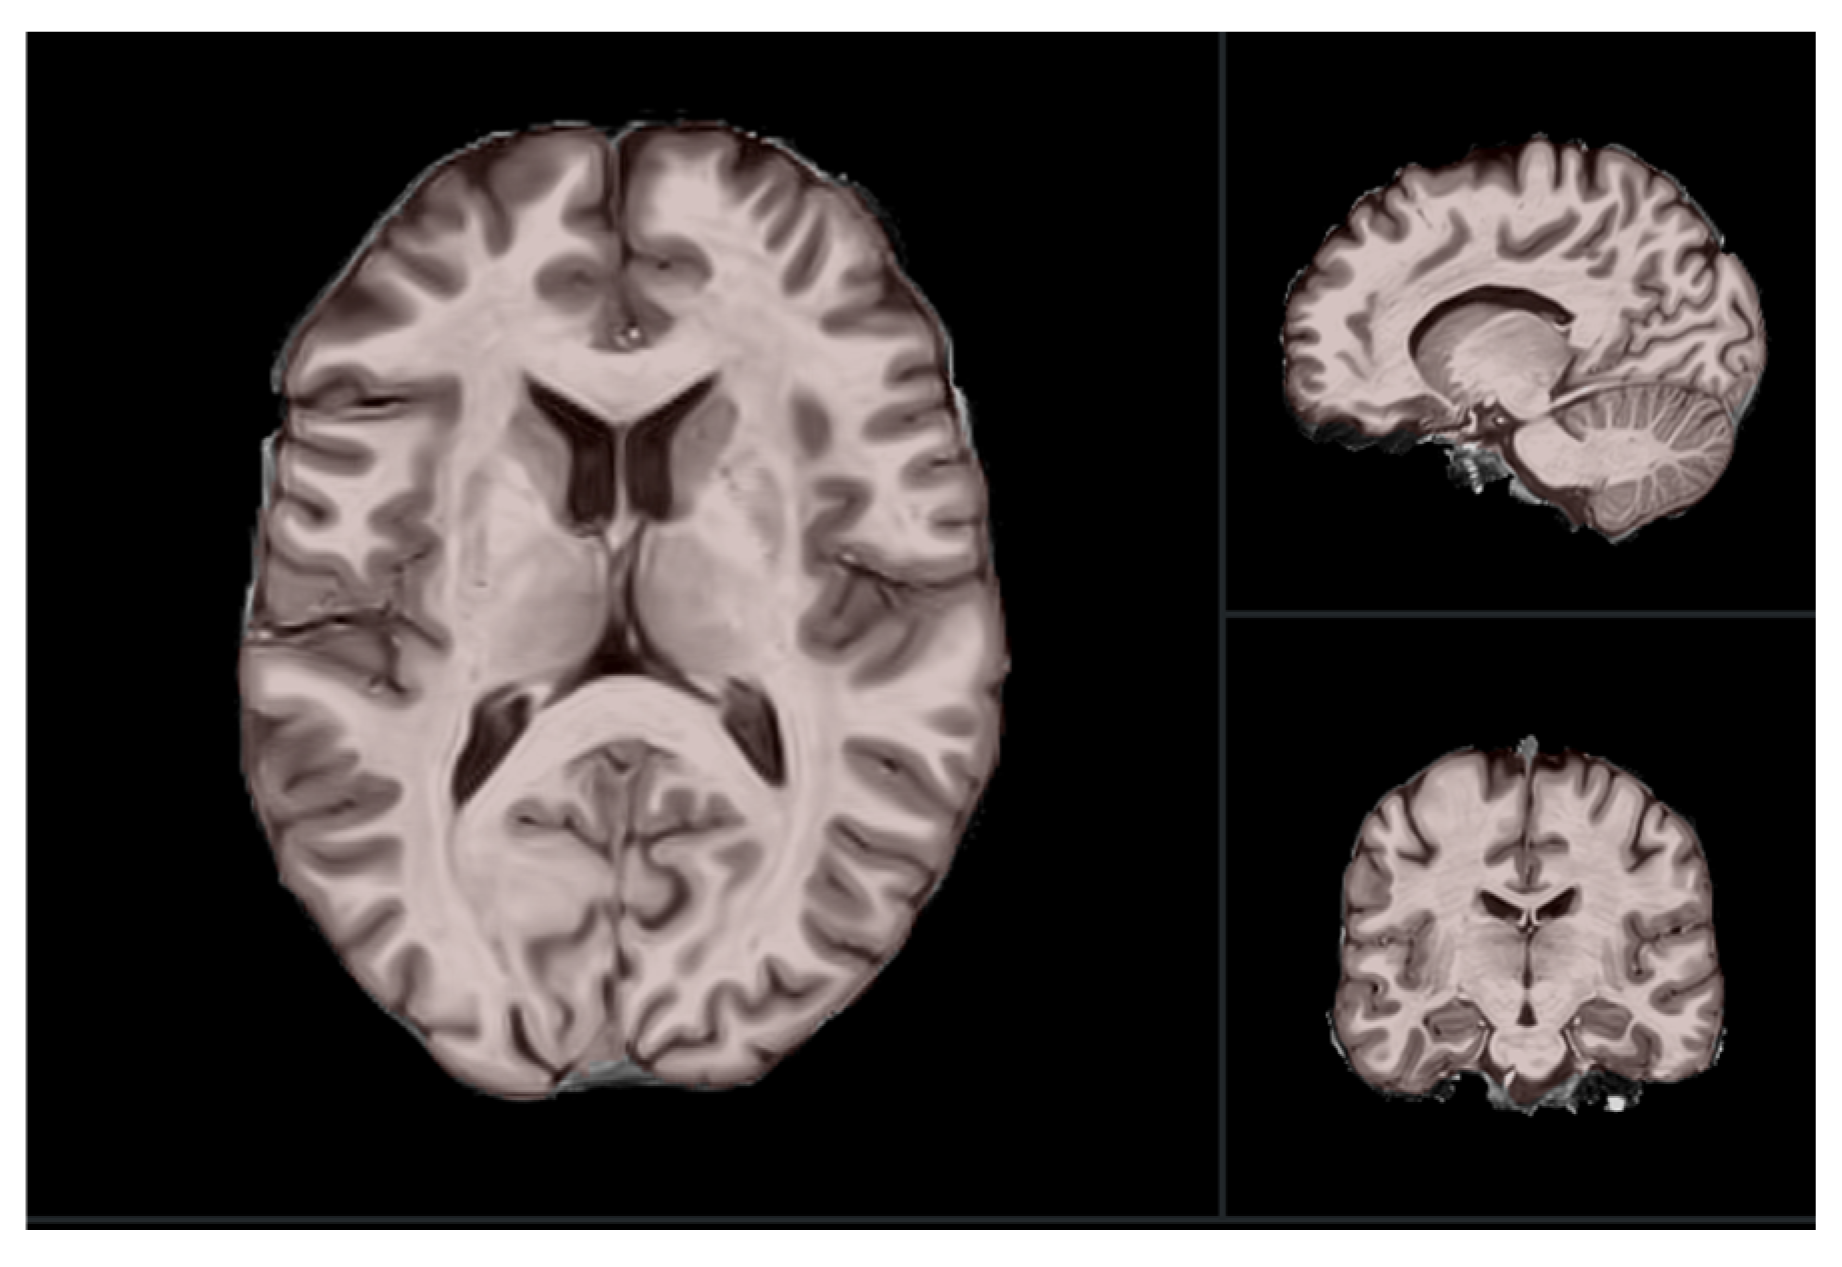

2.2. MRI Data Acquisition

2.3. Pre-Processing Methods